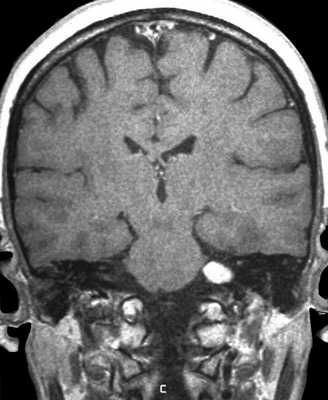

МРТ головного мозга. Т2-взвешенная корональная МРТ. Невринома слухового нерва, цветовая обработка изображения.

Шваннома (невринома) представляет собой инкапсулированную доброкачественную (градация I) опухоль, происходящую из дифференцированных неопластических шванновских клеток оболочек периферических нервов. Растут шванномы медленно и крайне редко малигнизируются. В целом шванномы составляют примерно 8% от внутричерепных опухолей. Пик частоты приходится на возраст 40-60 лет. Чаще всего встречаются шванномы слухового нерва (VIII пара), они составляет около 80 - 90% всех опухолей мосто - мозжечкового угла и около 3% от внутричерепных опухолей. Невриномы происходят из дистального по отношению к входу во внутренний слуховой проход части слухового нерва, обычно из вестибулярной (верхней) его ветви. Двухсторонние невриномы наблюдаются в 5% случаев и связаны с нейрофиброматозом типа II. Поскольку слуховой нерв (VIII пара) и лицевой нерв (VII пара) тесно связаны в начальной части, то на МРТ эти опухоли не дифференцируются. В 7-10% случаев шванноме сопутствует арахноидальная киста. Нейрофибромы отличаются от неврином большим числом соединительнотканных и нервных волокон, а также отсутствием капсулы. Пик частоты приходится на возраст 40-50 лет. Опухоль несколько чаще встречается у женщин. Для неврином слухового нерва характерна сенсоневральная тугоухость, шум в ушах и нарушение равновесия.

На Т2-взвешенных МРТ головного мозга невриномы имеют округлую или овальную форму, изоинтенсивны или слегка гиперинтенсивнее белого вещества, хорошо видны на фоне яркого ликвора цистерны. Крупные опухоли могут подвергаться кистозной дегенерации и включать сосуды. Мелкие невриномы имеют компонент во внутреннем слуховом проходе и как бы “утолщают“ нерв на МРТ изображениях. Как показывает опыт МРТ СПб полностью внутриканальцевые невриномы встречаются редко. МРТ в СПб при шванномах мы проводим обычно с контрастированием. Контрастирование неврином при МРТ с контрастированием хорошее, обычно однородное. Нельзя забывать, что во внутреннем слуховом проходе также может быть воспалительный процесс (неврит), приводящий к сходной клинической симптоматике. При МРТ неврит виден как отёк нерва, имеется контрастное усиление на МР томограммах.

МРТ головного мозга. Невринома слухового нерва слева с внутриканальцевым компонентом. Аксиальные Т1-зависимая МРТ, Т1-зависимая МРТ с контрастированием, и корональная Т1-зависимая МРТ с контрастированием.